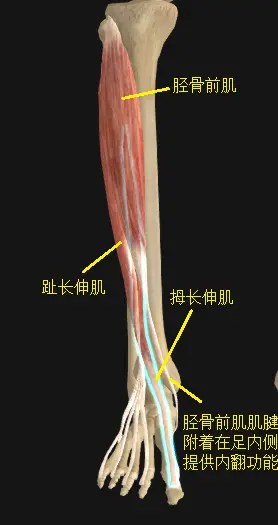

踝关节的背屈肌有胫骨前肌,拇长伸肌,趾长伸肌。

足踝的内翻肌有胫骨前肌和胫骨后肌(上图可见)。

足踝的内翻肌有胫骨前肌和胫骨后肌(上图可见)。